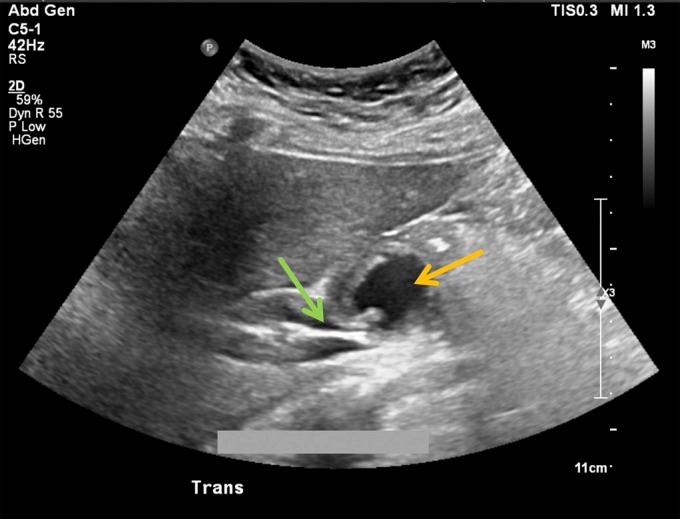

成功微创治疗导致肝外胆管受压的胃十二指肠动脉假性动脉瘤

Successful Minimally Invasive Management of a Gastroduodenal Artery Pseudoaneurysm Causing Extrinsic Bile Duct Compression.

Gastroduodenal artery (GDA) pseudoaneurysms are rare clinical entities that typically develop in the setting of chronic inflammation of the pancreas, although idiopathic pseudoaneurysms can occur. Although GDA pseudoaneurysms carry the risk of rupture with resultant hemorrhage, they seldom are reported to cause biliary obstruction. We report a unique case of biliary obstruction secondary to extrinsic compression of the bile duct by a GDA pseudoaneurysm successfully managed by nonoperative means.

摘要

胃十二指肠动脉(GDA)假性动脉瘤是一种罕见的临床病症,通常在胰腺慢性炎症的背景下发生,不过也可能出现特发性假性动脉瘤。尽管GDA假性动脉瘤有破裂并导致出血的风险,但很少有报道称其会引起胆管梗阻。我们报告了一例独特的病例,该病例为GDA假性动脉瘤对胆管造成外部压迫继发胆管梗阻,通过非手术方法成功治愈。